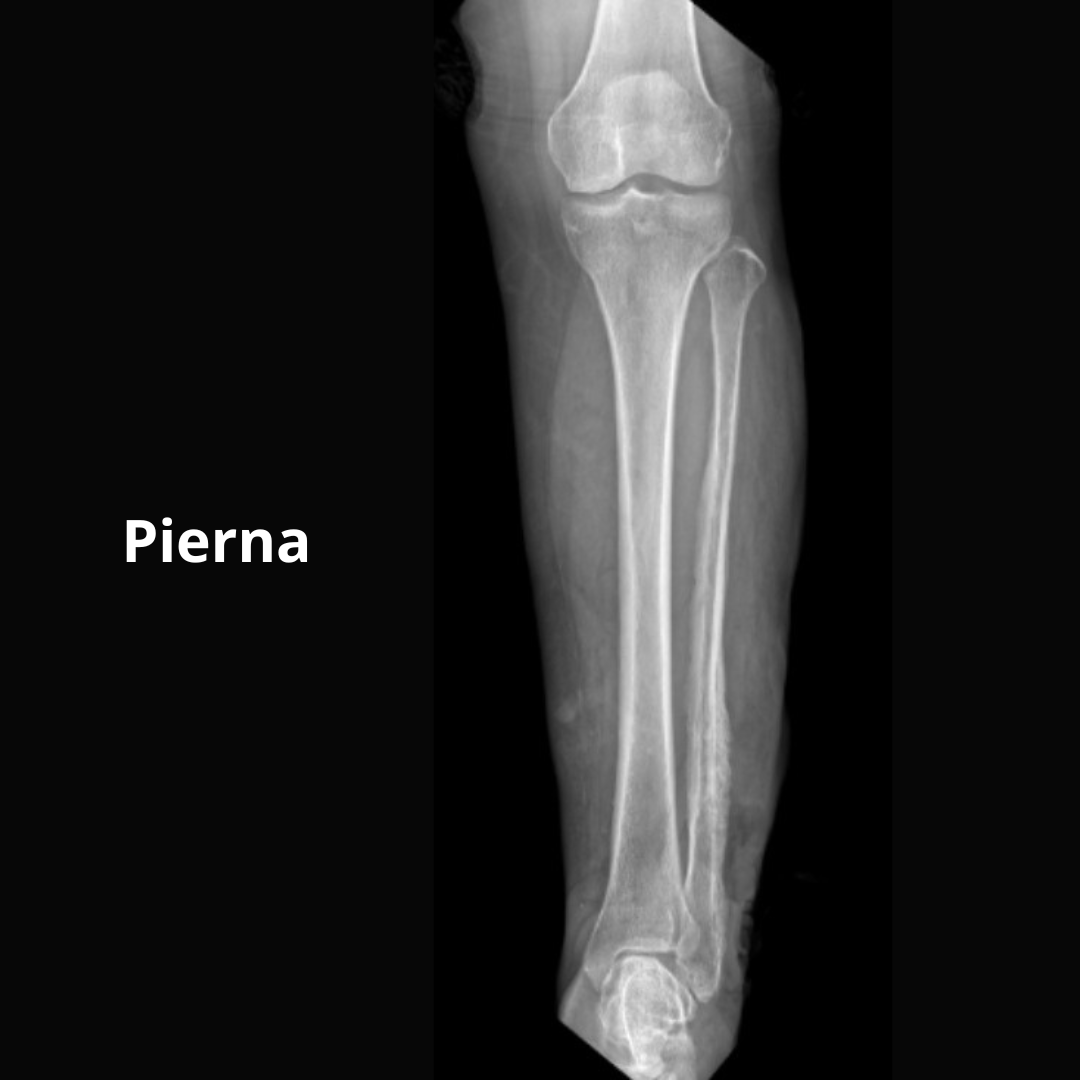

- Pierna ll O Derecho O Izquierdo O AP y Lateral

- Pierna ll O Der O Izq O AP y Lateral